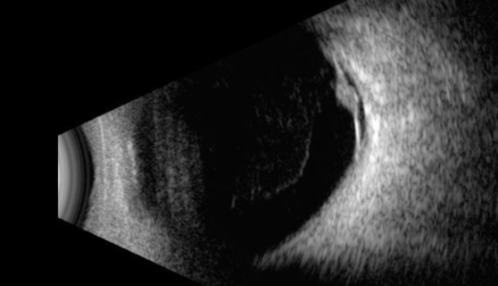

Retinal Angioma

53 year old female with no-symptoms and no significant medical history (or family history)

Retinal Angioma with Exudates